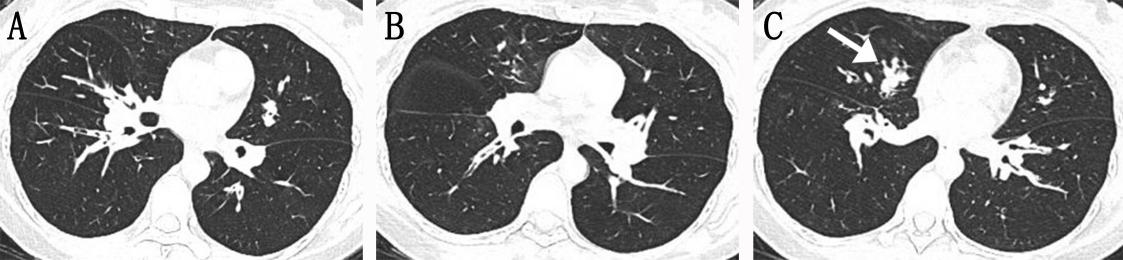

哮喘型COPD-IPA的胸部CT表现

图像来自一位45岁女性COPD-IPA患者,因“反复咳嗽、咳痰3月余,呼吸困难1周”入院。肺功能检查提示中重度阻塞性通气功能障碍。胸部CT(A、B、C)显示多发支气管黏液栓导致气道阻塞及中心性支气管扩张。